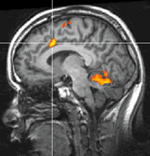

El grupo dirigido por DeCharms -con investigadores de las universidades de Stanford y Harvard-MIT- publicaron on line en diciembre de 2005 un estudio sobre la regulación central del dolor, utilizando un sistema de visualización directa de la imagen del dolor en la corteza del cíngulo.

Esto lo lograron por medio de una pantalla localizada dentro del equipo de fMRI que el sujeto de estudio podía observar durante la estimulación dolorígena. Individuos normales y aquellos con dolor crónico, pudieron reducir o incrementar el dolor por medio de la visualización de dicha imagen.

Los investigadores establecieron un sistema análogo para medir la intensidad del dolor al simular el fuego de una hoguera, cuya intensidad o brillantez variaba de acuerdo a la voluntad del sujeto de experimentación y que él veía directamente en la pantalla dentro del equipo de resonancia.

En otras palabras, la zona rostral de la circunvolución del cíngulo que representa la zona dolorígena-afectiva, aumentaba o disminuía en su brillo de acuerdo a la voluntad del sujeto, una vez entrenado para hacerlo por medios puramente mentales. Lo último se reflejó en la percepción del dolor.

Al reducir el brillo de la “hoguera”del cíngulo, el sujeto normal o el enfermo sentían menos dolor y viceversa. (Figura 2).

De gran importancia es el hecho que ningún individuo pudo ejercer influencia sobre la corteza del cíngulo sin ver de manera simultánea el fMRI en la pantalla localizada dentro del equipo de resonancia, si vio una imagen falsa que perteneciera a otro miembro del grupo investigado, o si vio otra área de su cerebro pero diferente al área del cíngulo .Los pacientes con dolor crónico informaron una mejoría en su dolor luego de la autoterapia ‘lumínica” cerebral. ¡Ver para creer!

| Figura 1: Receptores de los opiodes ocupados por endorfinas inducidas por el placebo y visualizados por medio de moléculas radioactivas (PET SCAN). | Figura 2: La intersección de las líneas incide sobre el área anterior de la circunvolución del cíngulo .Los sujetos investigados pudieron aumentar o disminuir la actividad sobre esta región voluntariamente por medio de observación directa, alterando la percepción dolorígena (fMRI). |